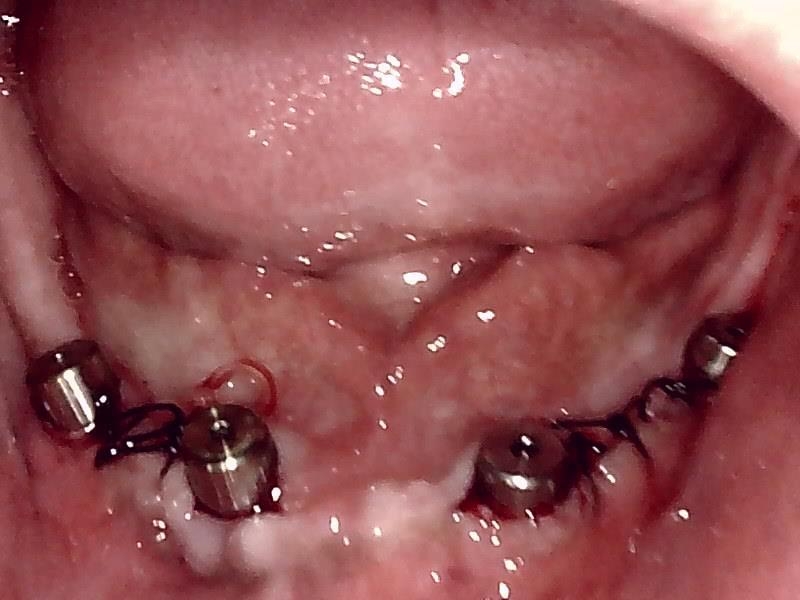

縫合した状態です。

ヒーリングアバットメント装着して歯肉を縫合した状態です。

抜糸後の状態です。